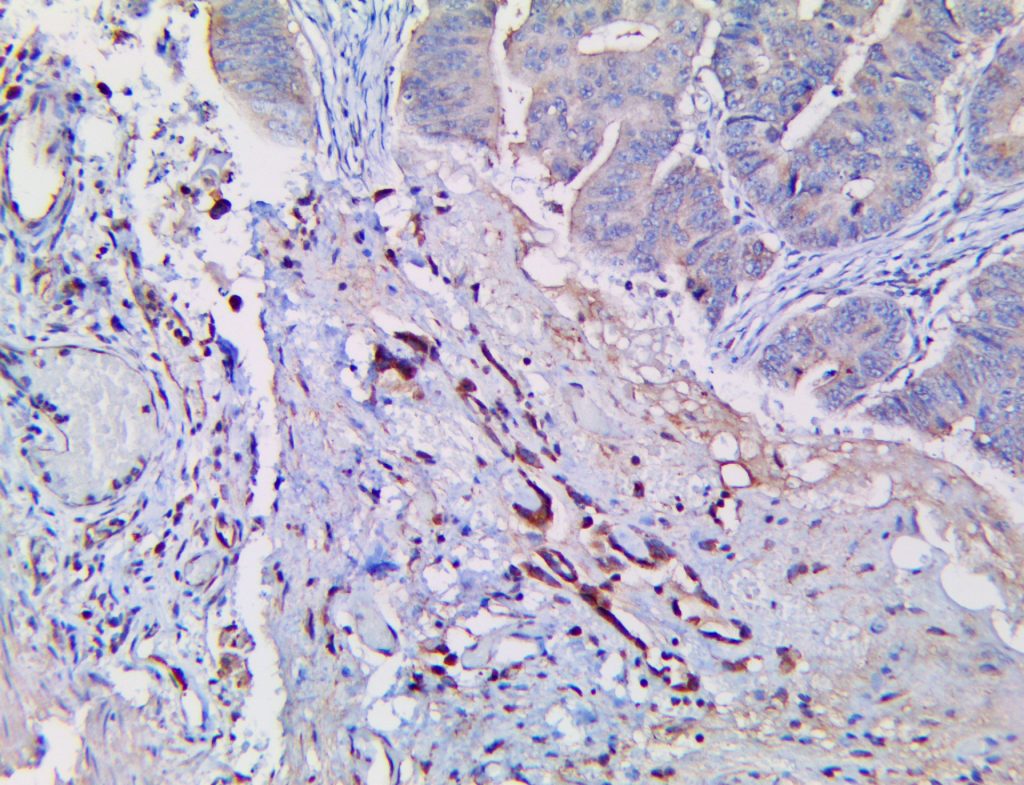

It is the ICU physician who is most likely to witness one of the deadliest manifestations of the abnormal immunological response, the cytokine storm syndrome (CSS). This response is also referred to by some as the cytokine release syndrome (CRS). CSS is characterized by continuous activation and expansion of macrophage and lymphocyte populations, which secrete large amounts of cytokines, causing the cytokine storm. This massive cytokine release is akin to hemophagocytic lymphohistiocytosis (HLH) disease, a syndrome characterized by initial unchecked and persistent activation of cytotoxic T lymphocytes and NK cells.

Clinical and laboratory manifestations of HLH include fever, enlarged liver and/or spleen, neurologic dysfunction, coagulopathy, liver dysfunction, cytopenias (i.e., low levels of erythrocytes, leukocytes, and/or platelets), hypertriglyceridemia, hyperferritinemia, hemophagocytosis, and eventually diminished NK cell activity as the immune system becomes progressively paralyzed. HLH can be familial (primary HLH) or secondary to another disease process (sHLH), such as rheumatic disease, in which it is referred to as macrophage activation syndrome (MAS, characterized by elevated ferritin).